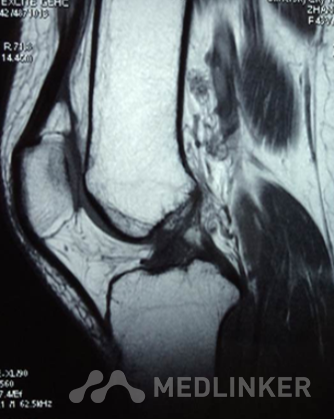

查体:左下肢无畸形,左膝关节无静脉曲张、肿胀等,皮温正常,关节间隙压痛,麦氏征(+),蹲走试 验(-),过伸试验(-),过屈试验(-),浮髌征(-),髌骨加压研磨试验(+),前抽屉试验(+) ,后抽屉试验(-),侧方应力试验(-),lachman征(+),关节活动度0-135度,股四头肌无明显萎缩 ,肌力正常;肢端血运、感觉、活动正常。双上肢及右下肢其余关节未见明显异常。 X线提示:左膝关节退行性变。 MR提示:左膝关节前交叉韧带内侧束损伤。

诊断 左膝关节前交叉韧带前内侧束断裂行左膝关节镜检,前交叉韧带分束重建术